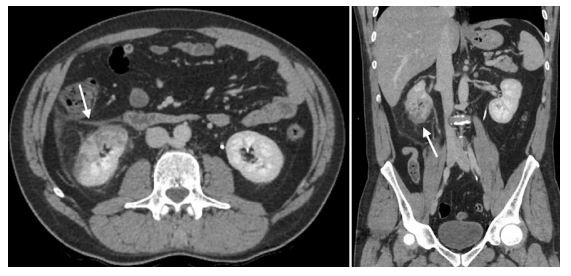

A 48-year-old male patient presented to our institution with symptoms of high fever (38 °C) and abdominal pain for 4 days. He had no respiratory tract symptoms and no abnormal findings on his physical examination and reported no history of respiratory problems. His laboratory workup revealed leukopenia (3.8×10−3 µ/L) and lymphopenia (1.2×10−3 µ/L). Additionally, the following parameters were abnormally elevated: d-dimer (0.7 µg/mL), lactate dehydrogenase (567 U/L), alanine aminotransferase (59 U/L), ferritin (577.8 ng/mL) and CRP (138.2 mg/L). Creatinine and e-GFR were within normal limits. The patient was sent to the radiology department for further evaluation with contrast-enhanced chest and abdominal CT exams. Chest CT demonstrated patchily, ground-glass per lobular opacities with reticular densities at the peripheral portions of both lungs (Fig. 1). Additionally, a reverse halo sign was present in the posterior segment of the right upper lobe. The CT findings were described as possible COVID-19 findings. There were no signs of pulmonary arterial embolism. On the abdominal CT, the right kidney showed patchily, sharply demarcated hypo enhancing and non-enhancing areas in the anterior part of the lower pole with increased heterogeneous linear densities in peri and pararenal areas (Fig. 2). No other abnormalities were seen on the abdominal CT. As a result of clinical and abdominal imaging findings, segmental renal infarct was the patient’s leading diagnosis and he was admitted to our hospital. In the light of chest and renal findings, a polymerase chain reaction (PCR) test from nasal swab for COVID-19 was ordered and urine analysis with urine culture tests was performed. PCR test returned positive for COVID-19 infection. No abnormalities were detected on urinalysis and urine culture was negative. The patient did not develop any respiratory symptoms throughout his hospital course and did not require admission to the intensive care unit. He was treated with hydroxychloroquine and oseltamivir, according to the COVID-19 protocol of our community’s health ministry. In addition, given the renal findings on CT and the diagnosis of renal infarct, the patient was given low-molecular-weight heparin. After the fifth day of the medical treatment, the fever dropped, and his abdominal pain decreased. On the 9th and 11th days of hospitalization, nasal swab for PCR tests were repeated and the results had turned negative on both of those tests. Besides, all of his abdominal symptoms had resolved. Therefore, he was discharged and sent to quarantine at home.

Fig. 2 Right kidney demonstrates a sharply demarcated heterogeneous area containing non-enhancing and hypoenhancing portions (arrow). Significant perinephric stranding is also present.